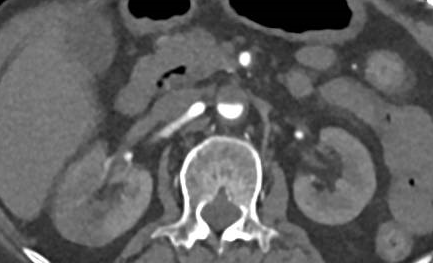

立即行心电图

检查,提示“心房颤动,V5、V6导联ST段抬高(图1)”;急查心肌酶谱及D-二聚体

,结果显示α-羟丁酸脱氢酶

、乳酸脱氢酶轻度升高,肌酸激酶及其同工酶正常,而D-二聚体显著升高至4.66mg/L(参考范围0–0.55mg/L)。

图1

医生迅速判断其为“急性ST段抬高型心肌梗死